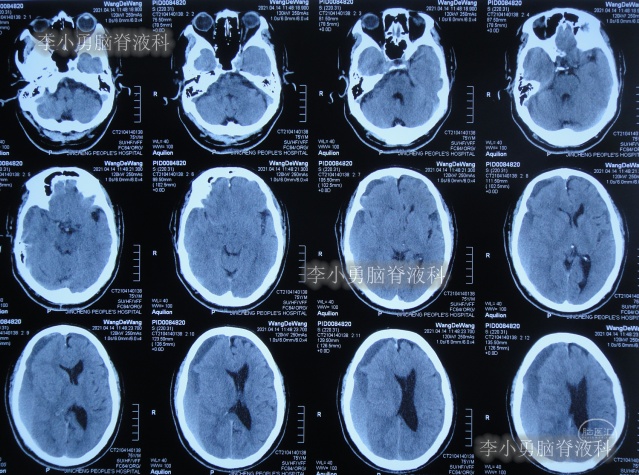

2020年10月29日(发病已8年),因症状一直没有得到改善且呈进行性加重趋势,查头部核磁示脑积水(图-1)。

图-1:2020年10月29日头部核磁